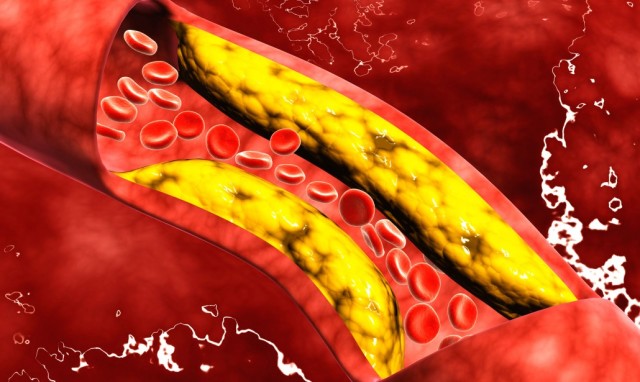

Le malattie cardiache sono la principale causa di morte in tutto il mondo. Il colesterolo alto porta ad arterie indurite che possono causare infarto o ictus. Quando le linee guida sono state riviste l’ultima volta cinque anni fa, si sono allontanate dall’uso dei valori del colesterolo per determinare chi ha bisogno di trattamento, verso una formula che tiene conto dell’età, dell’ipertensione arteriosa e di altri fattori per stimare in modo più ampio il rischio.

Infine, se non è chiaro se un paziente con colesterolo alto ha bisogno di cure, le linee guida suggeriscono un test dell’arteria coronarica per rilevare l’indurimento delle arterie che può aiutare a decidere. Si tratta di un tipo di raggi X con una dose di radiazioni simile a quella di una mammografia.